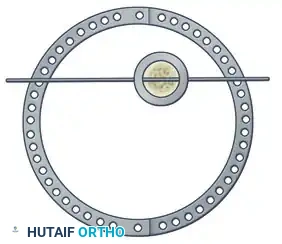

Step 3: Multi-Planar Fracture Reduction Using Olive Wires

Olive wires (wires with a small metal bead or "olive" forged into them) are powerful tools for translating bone fragments and achieving final reduction.

- Coronal Plane Correction: Use arched olive wires for final fracture reduction. For residual displacement in the coronal plane, place an olive wire in a transverse fashion (ensuring it passes through a safe anatomical zone).

- Apply tension to the wire without securing it tightly to the frame on the opposite side. The tensioner will pull the olive—and consequently the bone fragment—toward the tensioner, correcting the translation.

- Use continuous image intensification to ensure adequate reduction is achieved without over-translating the fragment.

- Once adequate correction is obtained in the coronal plane, secure the wire to the frame on the olive side.

- Sagittal Plane Correction: If further correction is required in the sagittal plane, connect another olive wire in an arched fashion. Tensioning this arched wire will impart a directional force vector to the bone, achieving final sagittal alignment.